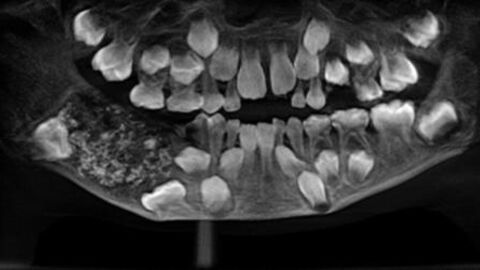

Behind the bleeding, a rare disease

Further medical tests have established that Liu Gofan may have been suffering from acute myeloid leukaemia or AML, a rare cancer of the blood and bone marrow. As his body was cremated, no further tests will be able to confirmor deny this. The mystery will remain.